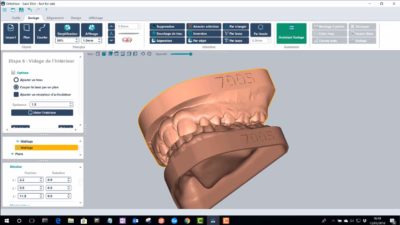

Le module Deltaface Aligner vous permettra la création de plaques occlusales transparentes.

Dans un premier temps, la segmentation des dents se fait de façon automatique. De même, le logiciel détecte automatiquement les collisions et génère ensuite automatiquement les étapes du traitement.

La numérotation et le positionnement des taquets sont tout aussi simples. Pour chaque étape, un modèle est créé par le logiciel et peut ainsi être imprimé en 3D. Ces modèles sont ensuite utilisés afin de créer des aligneurs transparents par thermoformage.